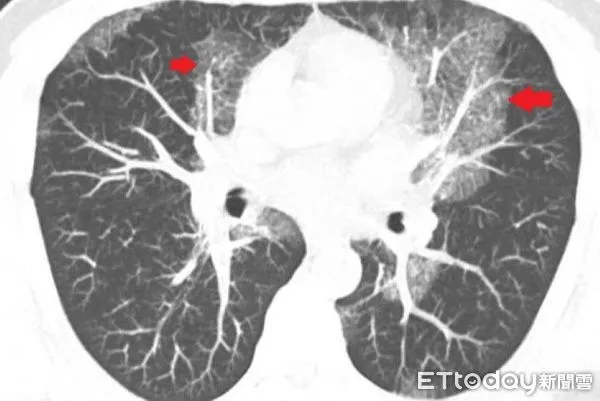

▲「肺部蛋白質沉積症」呈現大白肺狀況。(圖/台北慈濟醫院提供,下同)

收治該病例的台北慈濟醫院胸腔內科主任藍冑進指出,電腦斷層初步研判為肺部慢性發炎,但進一步的支氣管鏡檢查卻顯示氣道清晰無異常,連同細菌與黴菌等各項培養檢查也均為陰性,病因成謎,只能密切追蹤病況,3個月後卻發現雙肺白影惡化,最後魏先生接受電腦斷層導引下的肺部穿刺切片,才確診肺部蛋白質沉積症。

肺部蛋白質沉積症(Pulmonary Alveolar Proteinosis, PAP)是一種肺泡內充滿蛋白樣物質,嚴重阻礙氧氣交換的罕見疾病,發生率僅約百萬分之一。此疾病在早期常無明顯症狀,容易與肺炎、肺纖維化等疾病混淆,導致誤診與治療延誤,因此提高臨床警覺性至關重要。